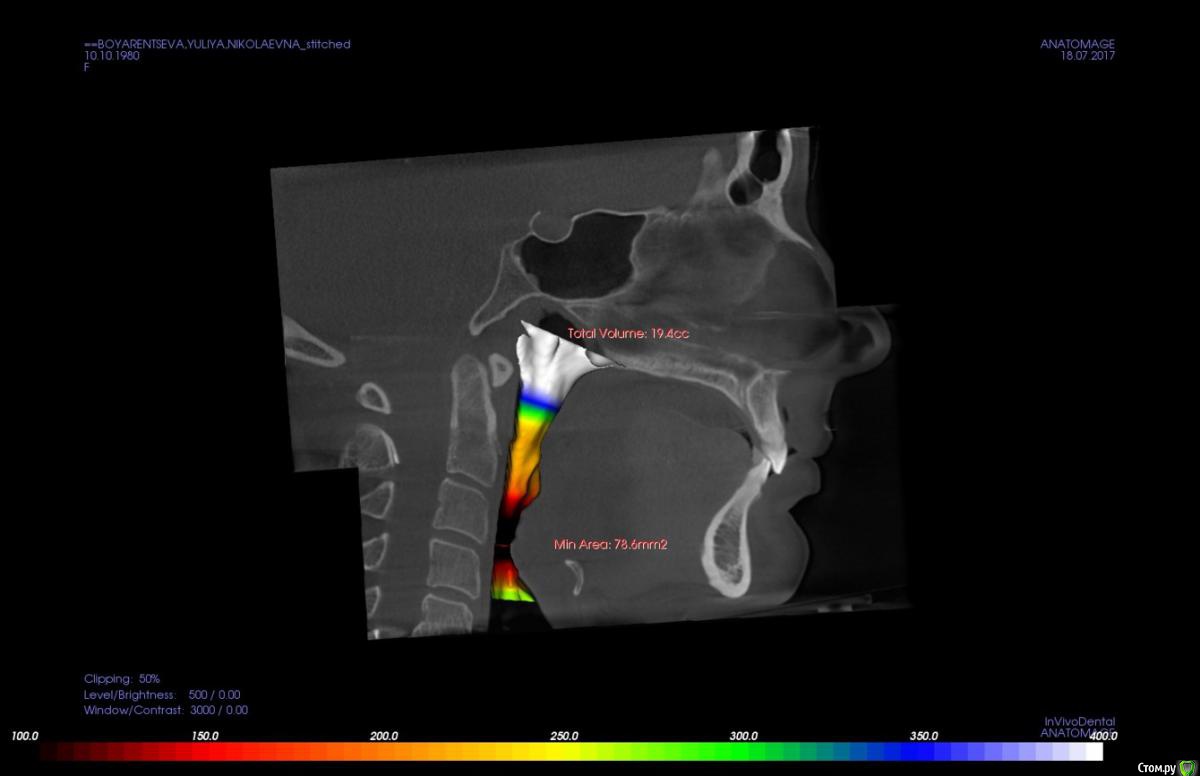

kapyulia Опубликовано 22 декабря, 2017 Поделиться Опубликовано 22 декабря, 2017 Добрый день! Могли бы Вы подсказать есть ли необходимость в удалении зубов (пятерки) с верхней челюсти? Спасибо за помощь. Ссылка на комментарий